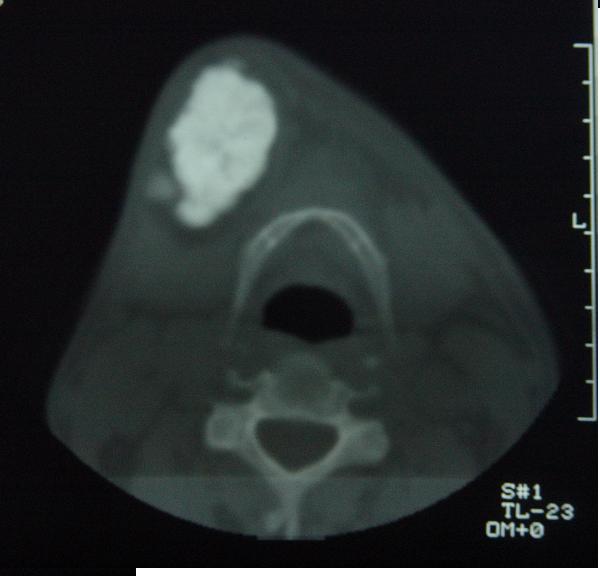

标题: CT12465:下颌骨肿瘤,请会诊 [打印本页]

标题: CT12465:下颌骨肿瘤,请会诊

发现下颌骨肿瘤近30年.逐渐增大.

考虑右侧下颌骨水平部及升部骨纤维异常增殖症可能性大。

造釉细胞瘤,没有特征性;半月切迹?骨间隔?多房性骨密度减低区,大小不等。鉴别;动脉瘤样骨囊肿,骨软骨瘤。本人,更倾向于---骨软骨瘤。

考虑右侧下颌骨骨化性纤维瘤。